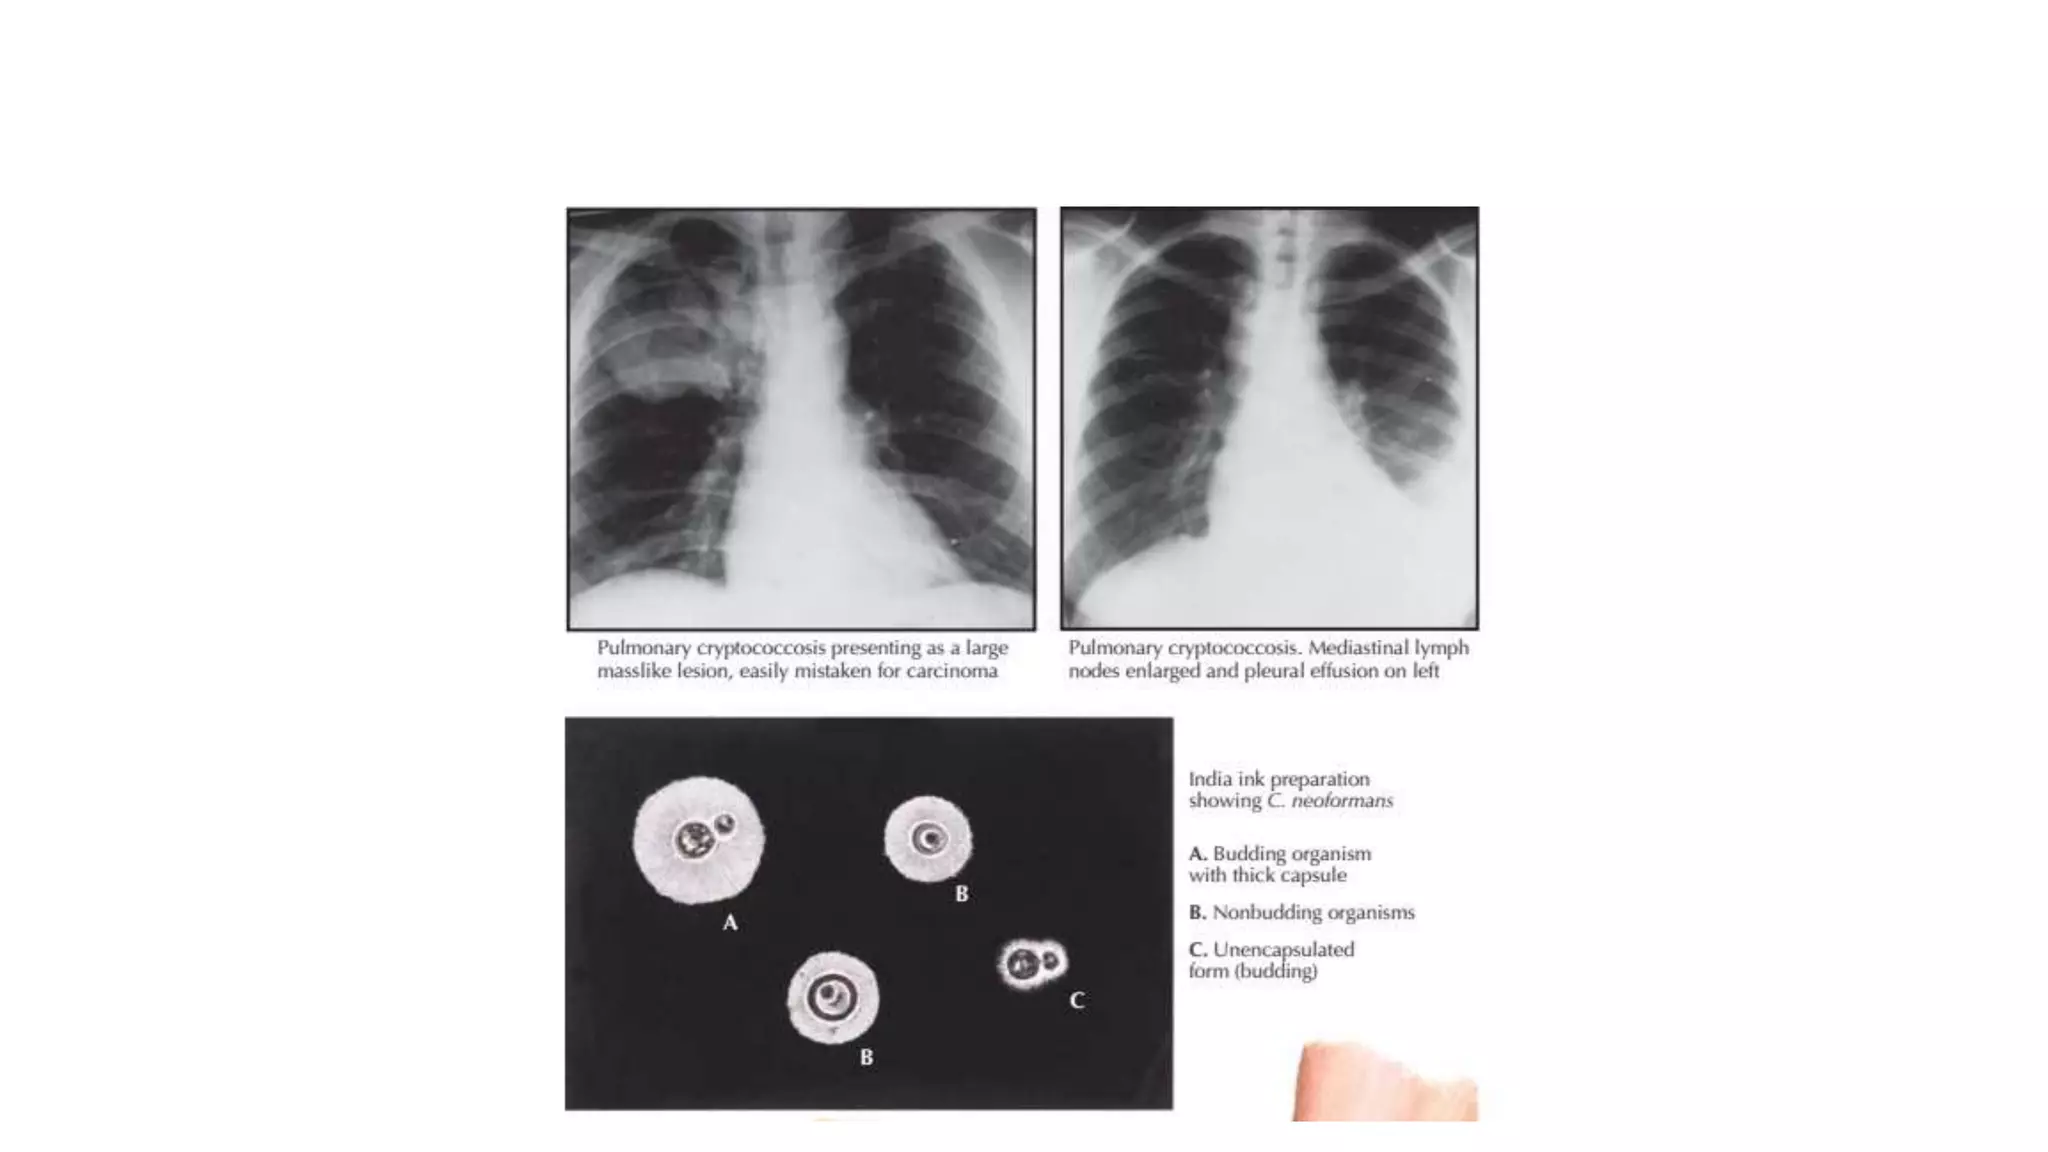

Cryptococcus

• Cryptococcus neoformans

• Encapsulated

• Prominent polysaccharide capsule

• Capsular halo  india ink preparn

• Cryptococcosis

• European blastomycosis

• TORULOSIS

• Most common SYSYTEMIC or invasive fungal ds in HIV infected person

(CD4<200)

• Pulmonary

• CNS  meningitis (MC)

• Intracranial space occupying lesion cryptococcoma

• In basal ganglia / head of caudate nucleus

• Cutaneous(molluscum like lesion) / osseous/visceral

Lab diagnosis

• Specimen  CSF or tissue specimens

• To demonstrate capsule Negative staining

• NIGROSIN / india ink

• Culture

• SDA

• bird seed agar (STAIBS MEDIUM)

• Antigen detection

• CRAg  cryptococcal Ag detection test in blood & CSF

• Rx

• AMB

• Flucytosine

• Fluconazole  aintenance therapy